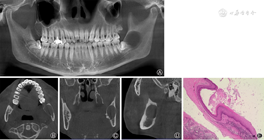

患者男性,25岁。因发现左下颌骨肿物2周,于2016年4月17日入院。2周前患者自觉左下颌后牙区疼痛,近1周出现左下唇麻木不适,2 d前张口中度受限。查体:口腔颌面部左右不对称,左侧颌面部肿胀,皮肤略红,压痛,左下唇麻木不适。双侧颌下区、颏下区及颈部未触及肿大淋巴结。X片示左侧下颌角见一长径约2.5 cm椭圆形低密度灶,边缘清晰锐利,无硬化,38近中阻生,位于其中(图1A)。CT示左侧下颌角见一大小约2.5 cm×2.5 cm×1.5 cm膨胀性骨质破坏区,边缘清晰,相邻骨质吸收变薄,但无明显硬化,病灶与下颌神经管关系密切(图1B~D)。全麻下行左侧下颌骨肿瘤切除术,术中见左侧下颌骨升支前缘及内侧骨质已破坏吸收,用裂钻去除部分骨质,暴露肿物,见肿物呈囊性,有白色豆腐渣样物质流出,囊壁与骨组织无粘连。大体标本:囊性灰白色肿物一个,大小约3.0 cm×2.0 cm×1.2 cm,囊壁厚约0.1 cm,囊内为灰白色皮脂样物。镜下见囊内壁为毛囊漏斗上皮,囊内含有排列呈板层的角化物质,可见角化不全细胞(图1E)。病理诊断:下颌骨表皮样囊肿。